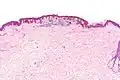

Micrograph of a dysplastic nevus showing the characteristic rete ridge bridging, shouldering, and lamellar fibrosis. H&E stain. | |